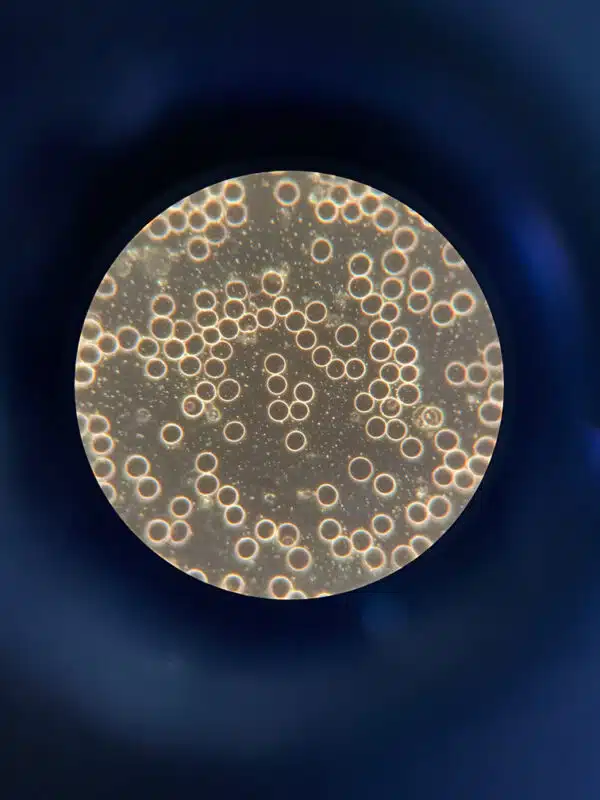

Die Durchschlagende Gesundheitswirkung von Rotwein Enthüllt: Die Rolle der Dunkelfeldmikroskopie

Eine Blutuntersuchung mittels Dunkelfeldmikroskopie eröffnet beeindruckende Einblicke in die gesundheitlichen Vorteile von Rotwein. Diese hochentwickelte Technik ermöglicht eine detaillierte Echtzeitanalyse lebender Blutproben. Durch die Streuung des Lichts wird das an den Blutbestandteilen gestreute Licht sichtbar gemacht, sodass Wissenschaftler dynamische Prozesse innerhalb menschlicher Zellen direkt beobachten können. Dies fördert eine präzise Beurteilung des zellulären Zustands und der Interaktion verschiedener Substanzen, wie der Antioxidantien in Rotwein. Mit der Dunkelfeldmikroskopie kann die Wirkung von Resveratrol, einem kraftvollen Antioxidans im Rotwein, auf die Blutzellen anschaulich dargestellt werden. Dadurch werden wertvolle Erkenntnisse über die potenziell krebshemmenden und herzschützenden Effekte des Resveratrols gewonnen, was die Bedeutung des Rotweins aus gesundheitlicher Sicht erheblich unterstreicht.